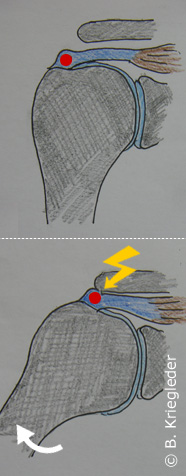

Abb 1; Skizzierte Lokalisation des Kalkes

Abb 2; Skizze - durch das seitliche anheben des Armes entstehen Schmerzen

Es handelt sich hierbei um eine umschriebene Ansammlung von Kalk (genauer Hydroxylapatit) im Inneren einer Sehne. Grundsätzlich kann sich Kalk in jeder Sehne des Körpers anlagern. In der überwiegenden Zahl der Fälle ist allerdings der Schulterbereich, bzw. die dort befindliche Supraspinatussehne betroffen. Die häufigsten ist das an einer Stelle knapp neben dem Sehnenansatz am Schulterkopf der Fall (Abb 1).

Grundsätzlich muss ein Kalkdepot keine Schmerzen verursachen. Viele Menschen leben völlig beschwerdefrei mit einem Kalkdepot. In vielen Fällen verursacht es aber Schmerzen. Durch die Kalkansammlung wird die Sehne in dem entsprechenden Bereich aufgerieben und kann somit nicht mehr problemlos unter dem Schulterdach durchgleiten wenn der Arm seitlich angehoben wird (Abb 2). Es kommt durch die ständige Reibung zu einer Reizung des Schleimbeutels, der sich zwischen Sehne und Schulterdach befindet. Diese ständige Irritation führt letztlich zu chronischen Schmerzen. Typisch für die Kalkschulter sind Schmerzen, die in den Oberarm ausstrahlen, vor allem dann wenn der Arm seitlich angehoben wird. Häufig treten auch in der Nacht Schmerzen auf. Die Beschwerden bleiben üblicherweise nicht immer gleich. Sie können manchmal beinahe oder ganz verschwinden, aber andererseits auch ganz massiv ausgeprägt sein, sodass der Arm schmerzbedingt kaum noch bewegt werden kann.